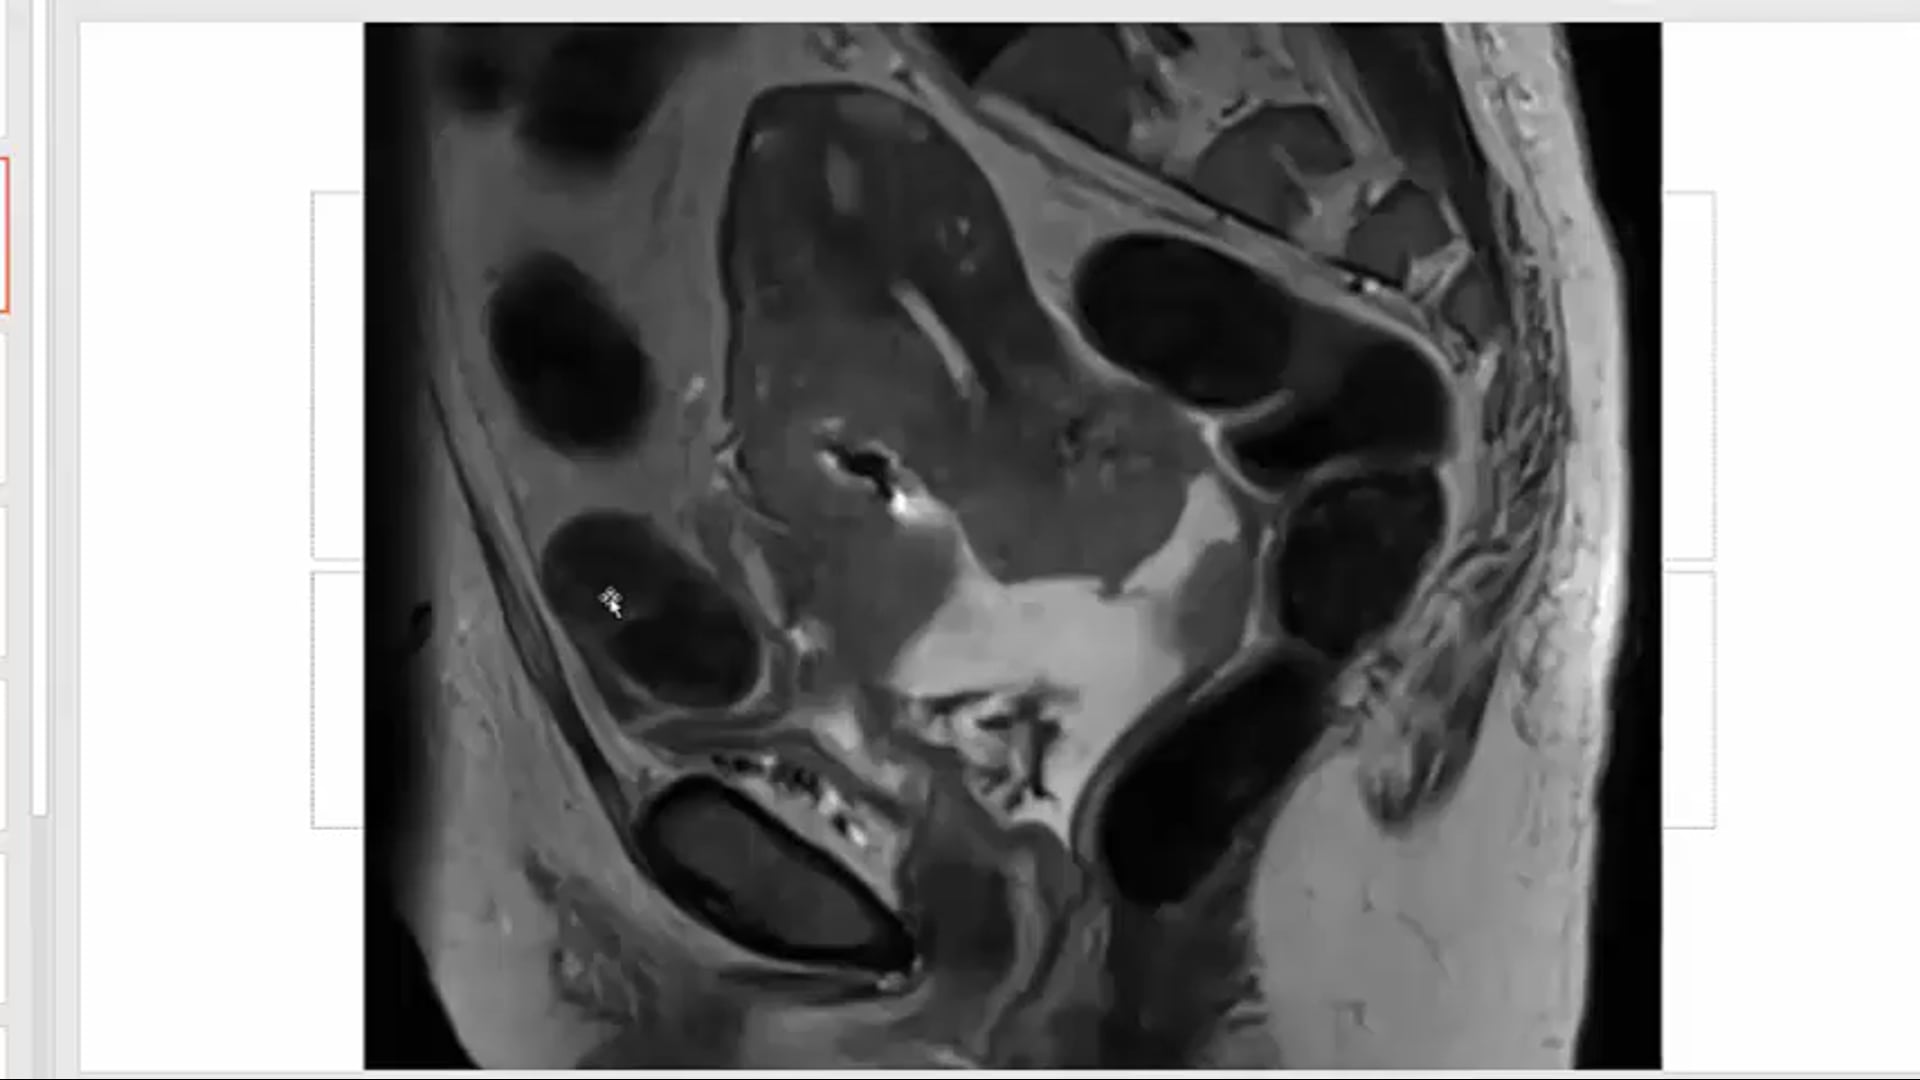

endometrial adenocarcinoma, para-aortic nodes, PET CT, diabetes, charcot arthropathy, groin nodes, pelvis, negative cervical margins, cisplatin, small bowel, Harkenrider, contouring, MRI, tumor, vaginal bleeding, relapse, persistence, cylinder, dose distribution, dosimetry, brachytherapy, fractio...

squamous cell carcinoma, dysplasia, PET, SIB, brachytherapy, endocervical, MRI, nodal location, inguinofemoral, right external iliac, CTV, deescalation, dosimetry, sigmoid, hysterectomy, concurrent chemoradiation, stenotic cervix, abdominal infection, external planning, avoid structure, antibioti...

chemotherapy, radiation therapy, sandwich regimen, brachytherapy, well differentiated endometrioid adenocarcinoma, neoadjuvant chemotherapy, small bowel, dilation, dosimetry, gross disease dose, MRI, cirrhosis, external beam radiation, Rotte Y applicator, CT scan, dual tandem, 3-D printing, endom...